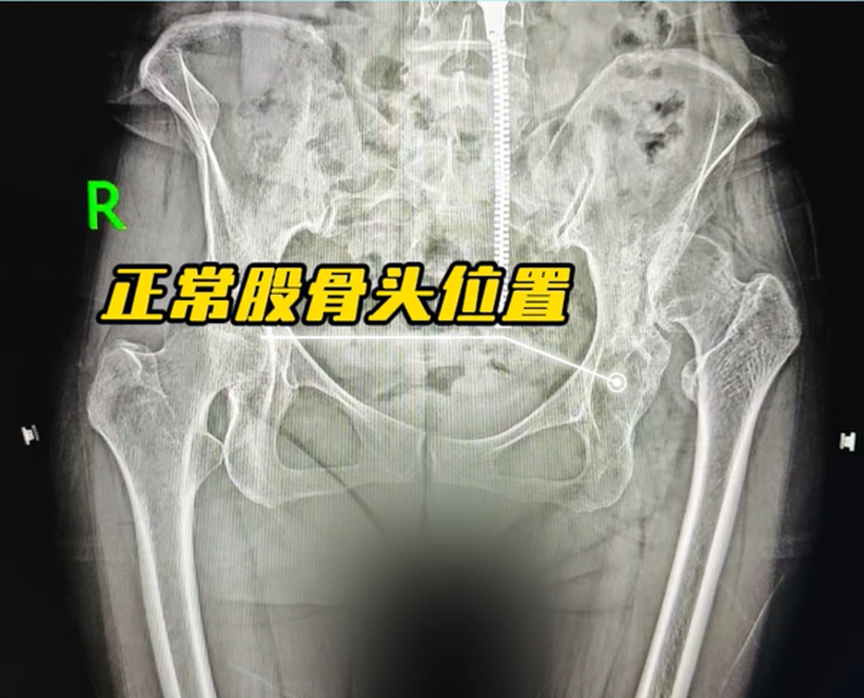

今年58岁的姜女士,因左侧髋关节先天发育不良,导致股骨头高度脱位,日常活动严重受限,行走举步维艰。为了回归正常生活,多年来,她辗转各地求医,却屡屡因治疗方案需进行截骨而却步。“我两条腿相差3到4公分,医生说截骨手术创伤大,术后还要长期卧床休养,我这个年纪实在怕承受这份痛苦和风险。”姜女士回忆道。

术前,机器人依托影像学数据,为姜女士量身定制了手术规划,精准锁定假体植入位置与角度;术中,医生借助机器人实时导航与毫米级精准计算,顺利完成关节复位、假体植入等一系列复杂操作,全程无需截骨,手术精准度控制在0.1毫米,最终手术圆满成功。